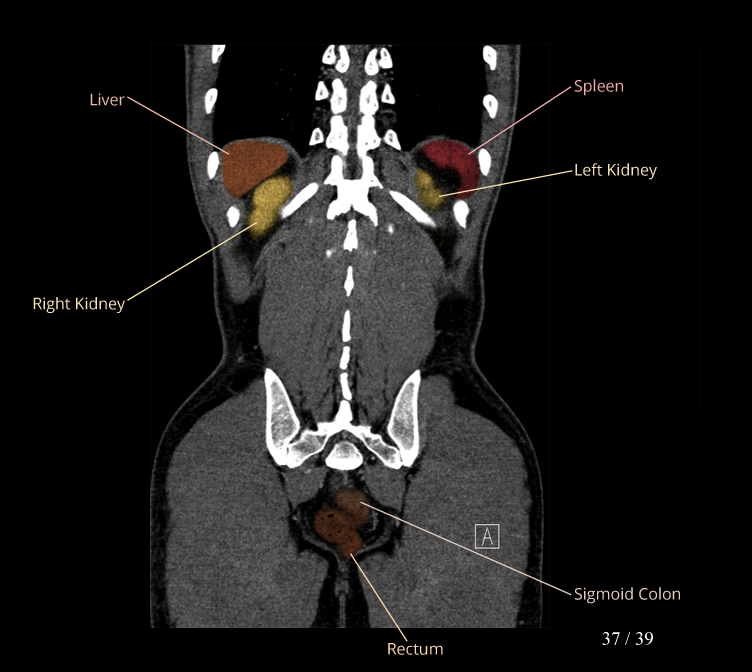

Body

Covers abdominal CT anatomy.